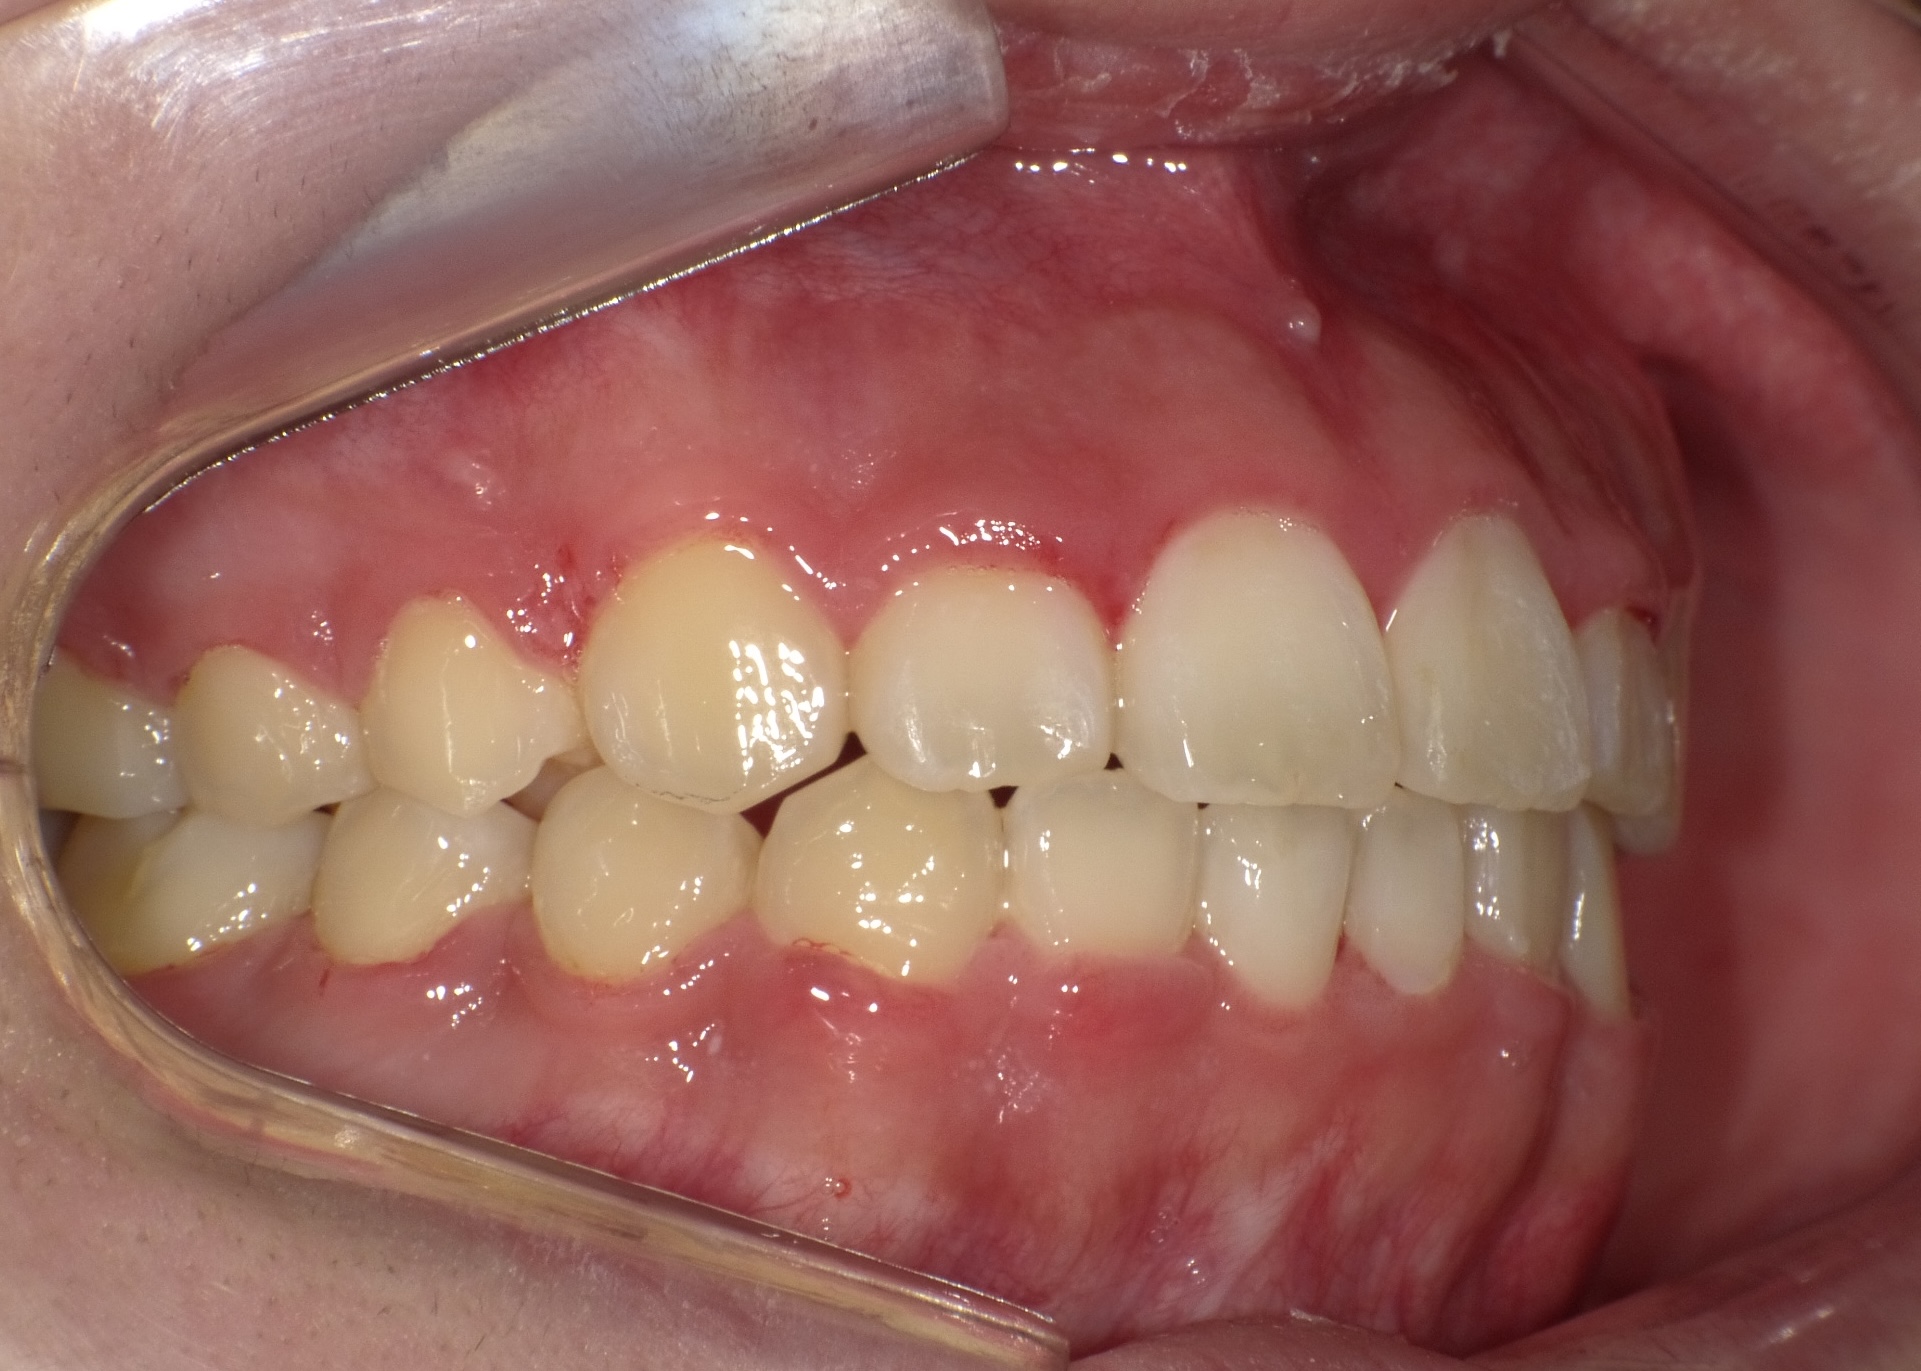

途中経過